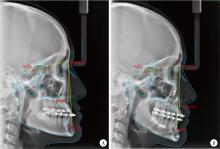

Figure 4

Preoperative (A) and 6-month postoperative (B) cephalometry indications"